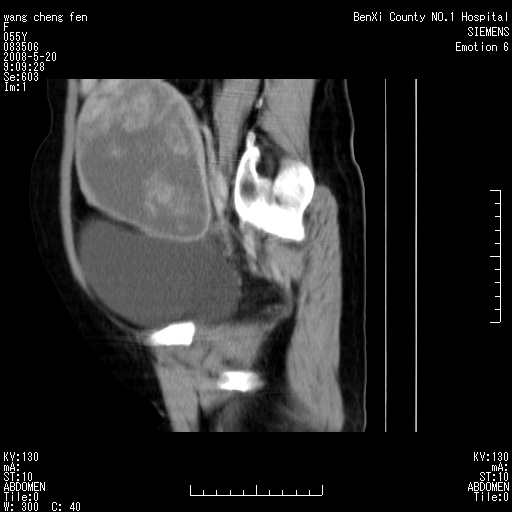

女、绝经后阴道流血3个月

左侧附件区巨大囊实性病灶,边缘光整,病灶囊壁较厚,增强示囊壁及实性部分明显强化,强化呈度与宫体实质大致相同,宫腔积液征像,未见盆腔积液等其他异常,考虑左侧卵巢囊腺癌,不除外囊腺瘤及浆膜下肌瘤坏死

左侧附件区巨大囊实性病灶,边缘光整,病灶囊壁较厚,增强示囊壁及实性部分明显强化,强化呈度与宫体实质大致相同,宫腔积液征像,未见盆腔积液等其他异常。绝经后阴道流血3个月,结合病史左侧卵巢囊腺癌首先考虑,宫腔扩大不除外累及。期待结果。

支持浆膜下子宫肌瘤.之前由于网络原因未看全图片,现在重看,宫颈见一类圆形低密度影,增强轻度强化,低于肌层强化,宫腔扩大,考虑宫颈癌伴宫腔积液可能性大.

囊实性肿块分隔厚度较大,厚薄不均,增强实性成分明显强化,有不规则阴道流血,卵巢囊腺癌可能性大。

1,宫颈部占位,宫颈癌?2,左侧附件区囊实性占位,界较清,实质部分强化明显。考虑浆膜下或阔韧带肌瘤囊变可能大。囊腺类肿瘤不除外。